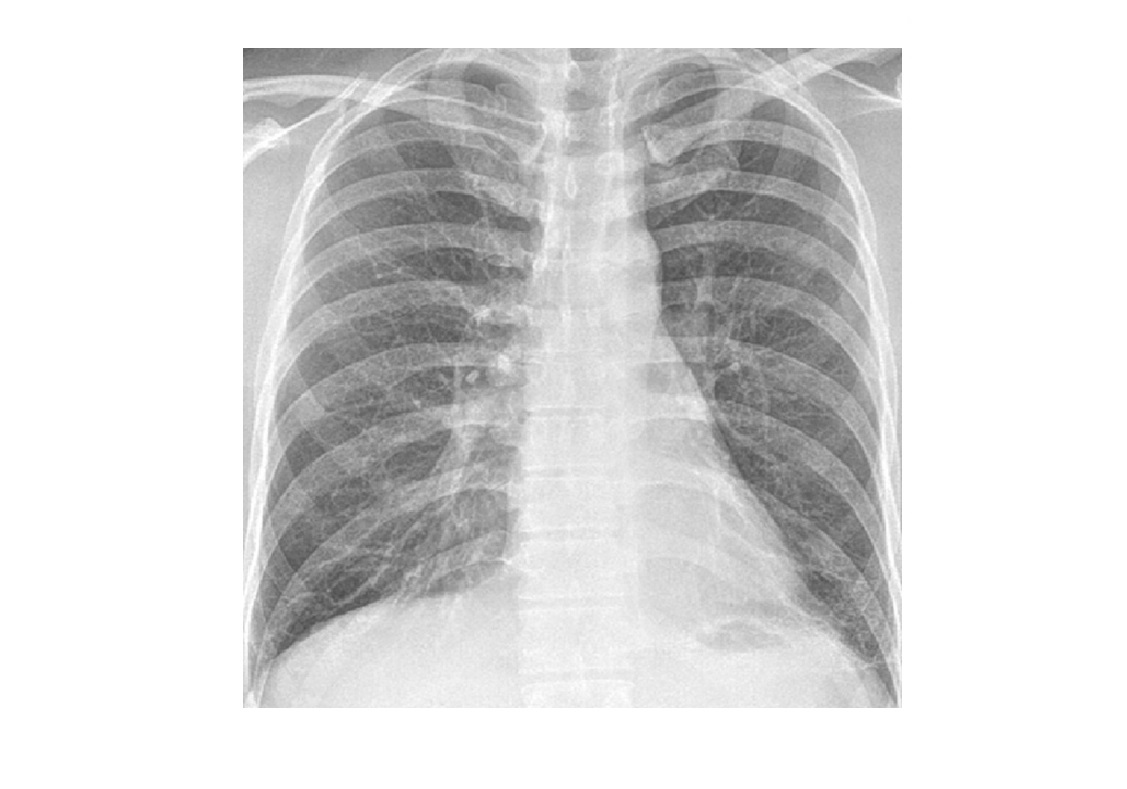

NSIP

lower lung zone predominant

CXR

bilateral, reticular opacities

CT

Absent (less) / microcystic honeycombing

Bilateral ground-glass &/or reticular opacities

Traction bronchiectasis/bronchiolectasis

Relative Subpleural sparing

peribronchovascular fibrosis

Most hunt for assocation/cause on CT

?dilated oesophagus - scleroderma

? joint disease - RA

?portcath/PICC - chemotherapy

sjorgens

HIV